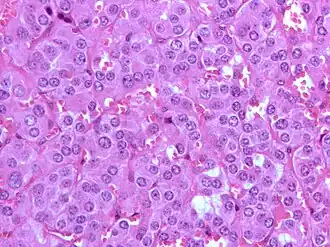

Een feochromocytoom is een zeldzame tumor van de chromaffiene cellen in het bijniermerg (90%) of chromaffiene cellen elders in het lichaam (10%). Indien de tumor gesitueerd is in het bijniermerg, is dat in 95% unilateraal, in 5% echter bilateraal. Het is een van de twee hoofdvormen van paragangliomen.